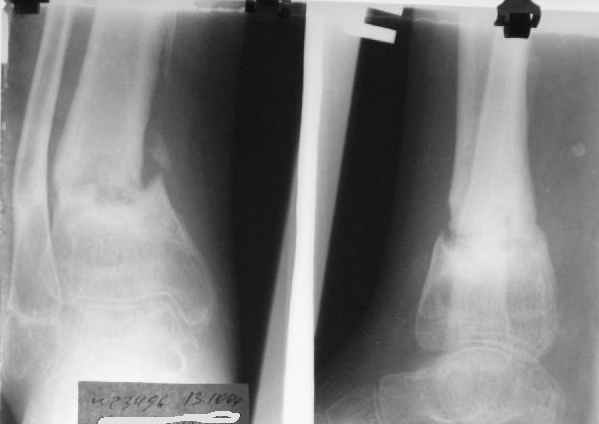

Так как речь зашла непосредственно о травме, см этапные

снимки. Как все было

Первичные

Вытяжение

Фиксация

в гипсе

Промежуточный